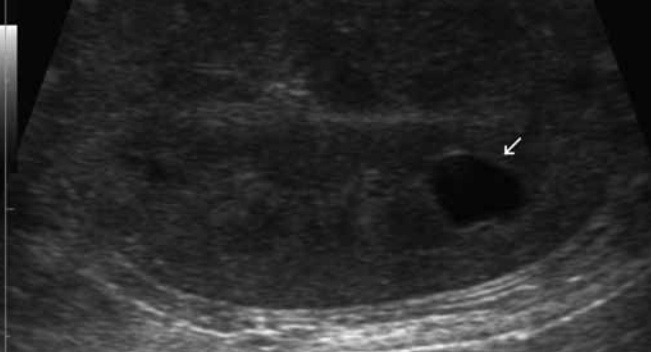

5-1. 신장 낭종(Renal cysts)(그림 8)

낭종은 피질 또는 수질에서 단일(그림 8) 또는 다발성(그림 9)으로 나타나며, 양측성으로 흔하게 나타납니다. 단일 낭종은 특히 노령묘에서 우연히 발견되며, 큰 다발성 낭종은 신장의 윤곽을 변형시키고, collecting system의 변위 및 왜곡을 가져옵니다.

초음파 영상의 특징은 둥글거나 타원형, 무에코의 내용물, 얇고 매끄러운 벽을 보이고, 원위 부위의 음향 증강을 보입니다.